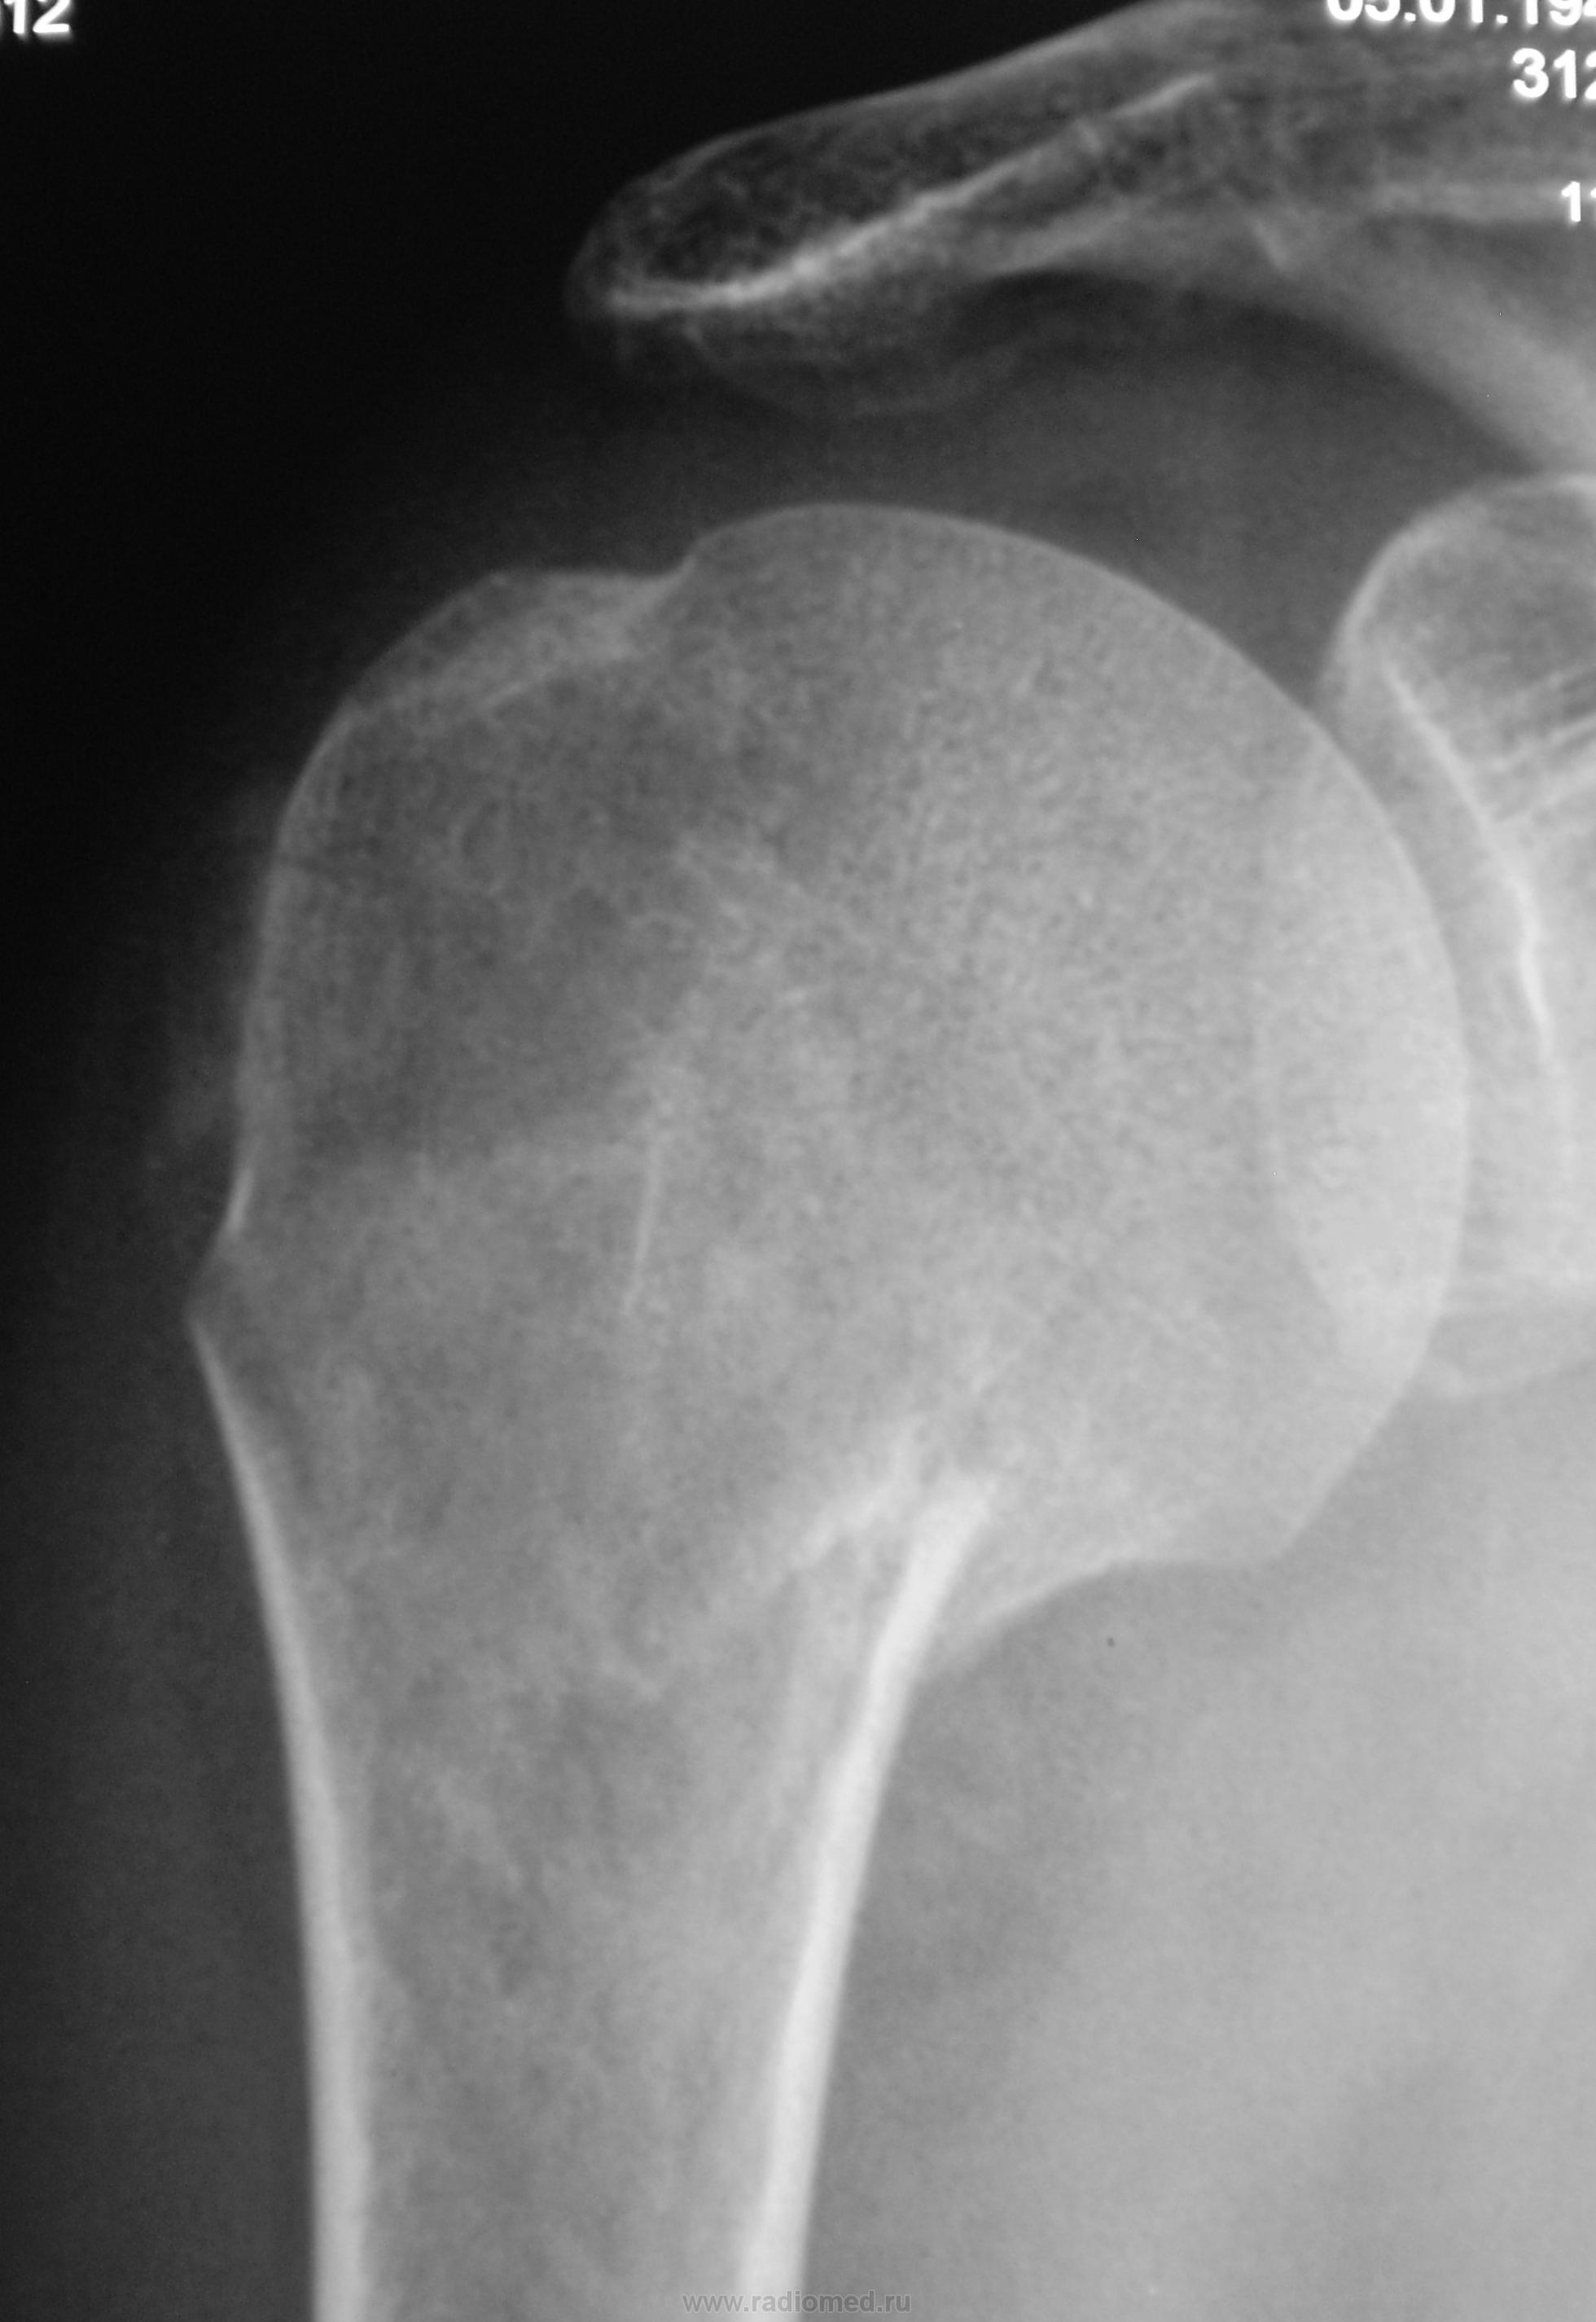

Перелом хирургической шейки плеча, отрыв коркового слоя у основания большого бугорка плеча, небольшая ротация головки плеча. Боковой снимок нужен.

+1. Увеличение расстояния между акромионом и головкой плечевой кости, вероятно за счёт повреждения ротаторной манжеты. Рекомендовал бы УЗИ, заодно и перелом большого бугорка можно подтвердить

перелом хир.шейки, осевая деформация допустимая, лечение наверняка будет косервативным.